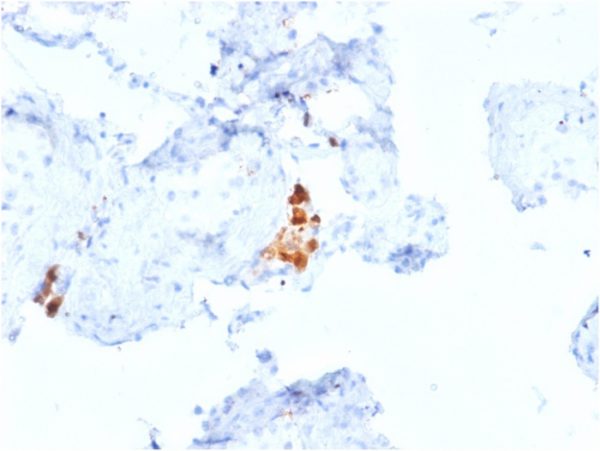

Formalin-fixed, paraffin-embedded human Mesothelioma stained with Calretinin Mouse Monoclonal Antibody (CALB2/2807).

It recognizes a protein of about 29kDa, which is identified as Calretinin (also known as Calbindin 2). Calretinin is a vitamin D-dependent calcium-binding protein involved in calcium signaling. It is present in subsets of neurons throughout the brain and spinal chord, including sensory ganglia. Antibody to calretinin is useful in differentiating mesothelioma from adenocarcinomas of the lung. It also aids in differentiating adrenal cortical neoplasms from pheochromocytomas.